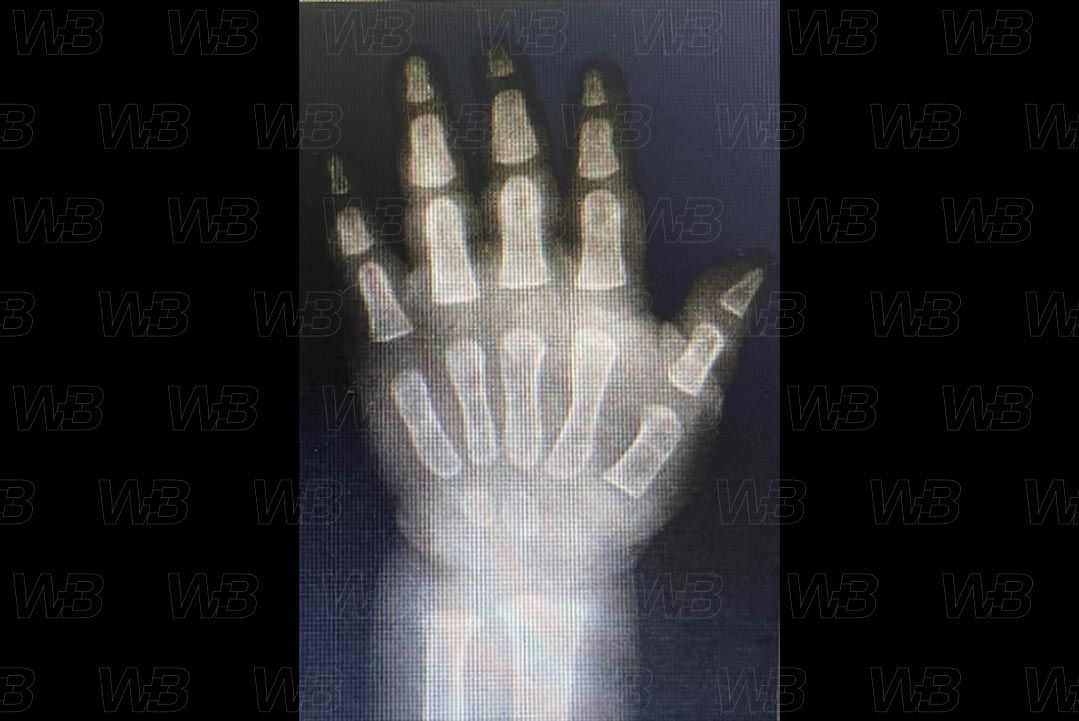

RADIOGRAFIA MÃOS E PUNHOS (IDADE ÓSSEA) [cms-watermark]

Feminino

1 ano e 3 meses:

• Epífise distal do rádio.